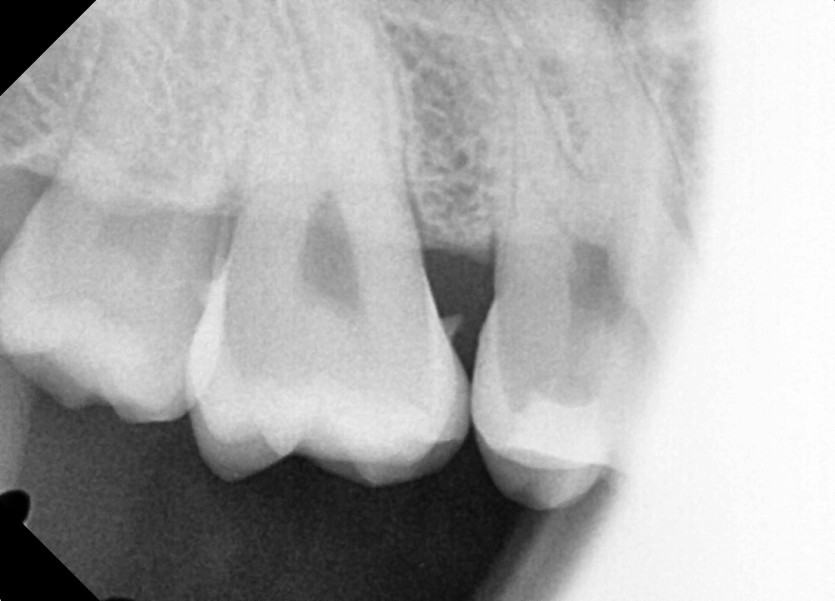

#18,48 사랑니 발치

구강 외과 전문의가 당일 발치했습니다.